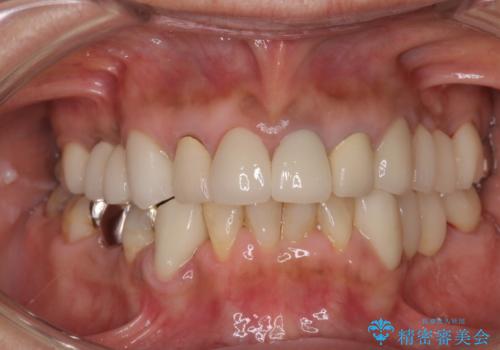

オールセラミッククラウンにすることで、色と形態をきれいにすることができました。